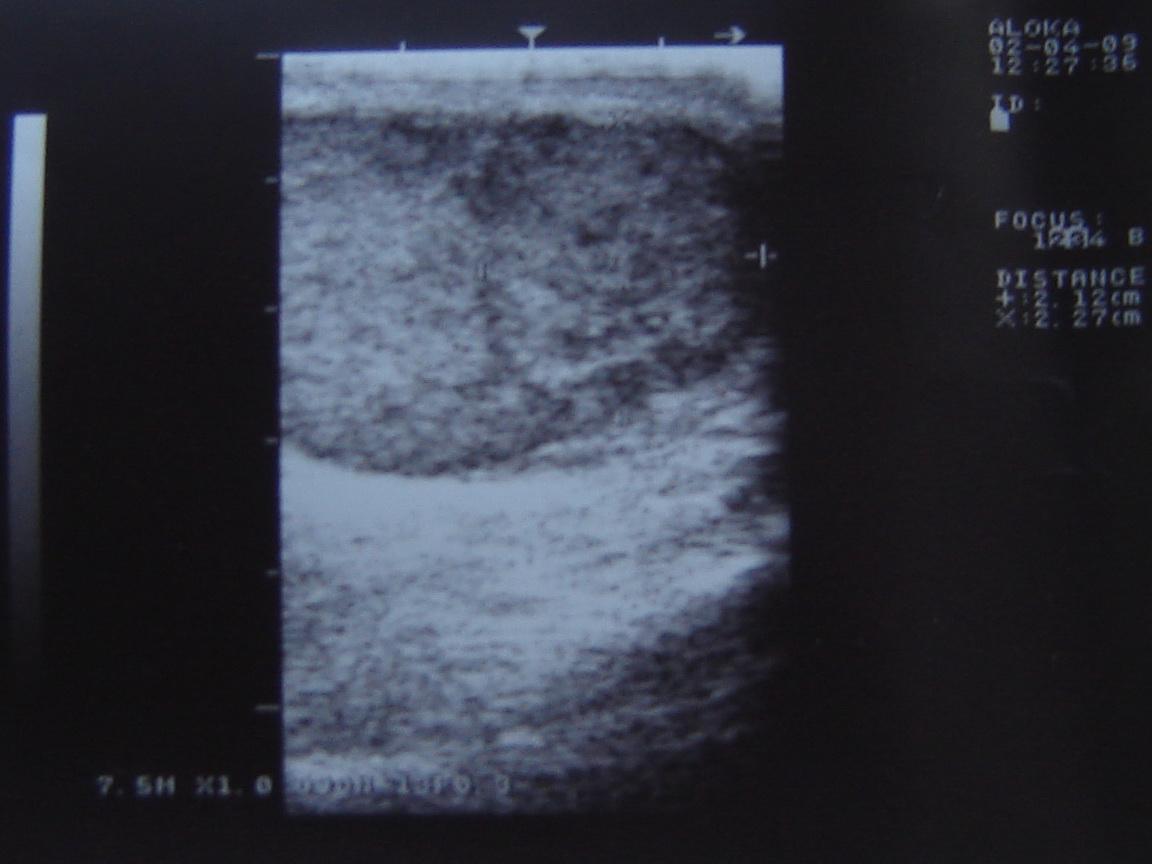

Уважаемый Алексей! По одному УЗИ не ставится диагноз. Надо сдать кровь на альфа-фетопротетеин и хореонический гонадотропин, сделать доппрерографию яичка. Проявите онконастороженность. Все лечится, если вовремя выявить. Напишите нам о результатах обследования.